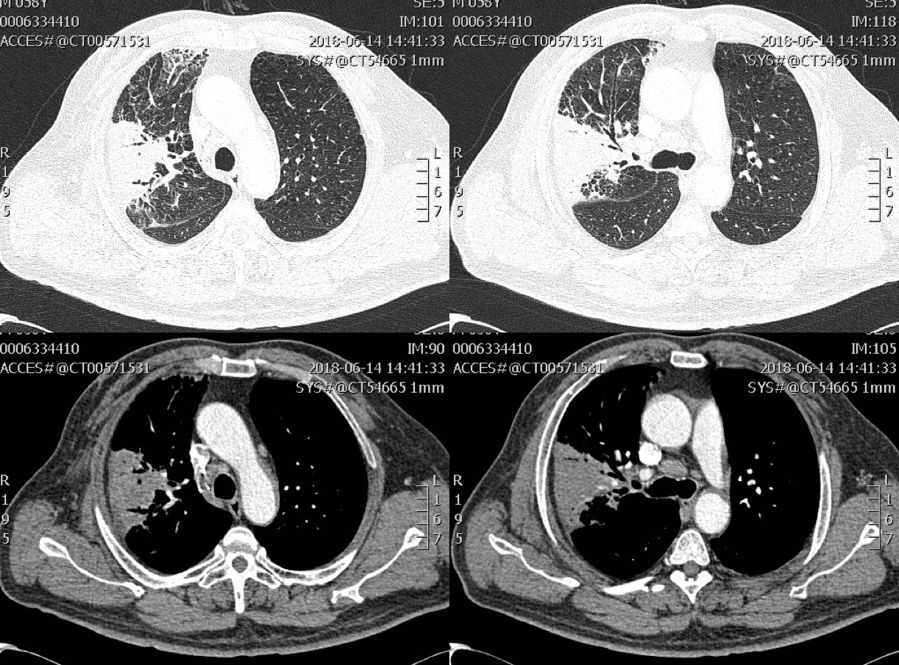

慢阻肺合并IPA影像表现为空洞、胸腔积液、结节、实变、浸润影。

影像学特点缺乏特异性,以「气道侵袭性」为主。

58岁男性患者,诊断慢阻肺3年。因反复咳嗽咳痰气促3年,再发加重伴咯血1+月入院。

体查:体温:36.0℃,脉搏:87次/分,呼吸:20次/分,血压:166/104mmHg;慢性病容,桶状胸,双侧呼吸动度对称,语颤无增强,双肺叩诊过清音,双肺呼吸音粗,右上肺少许干罗音,双肺未及胸膜摩擦音。

肺部CT:右上肺渗出